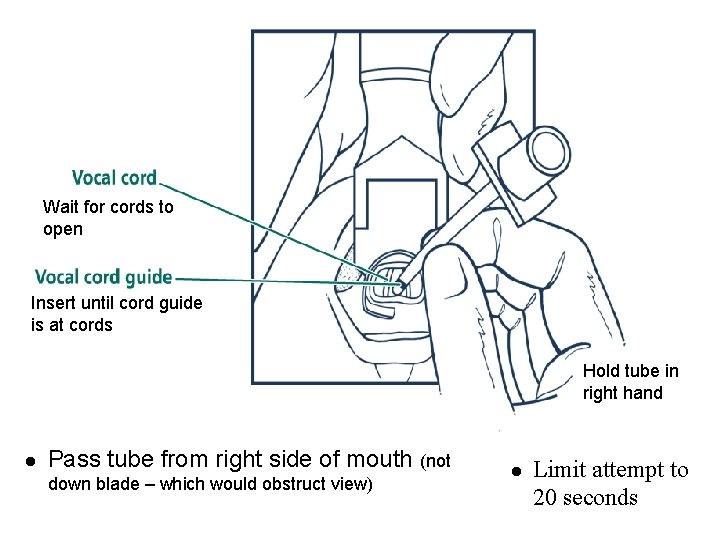

Wait for cords to open Insert until cord guide is at cords Hold tube in right hand l Pass tube from right side of mouth down blade – which would obstruct view) (not l Limit attempt to 20 seconds